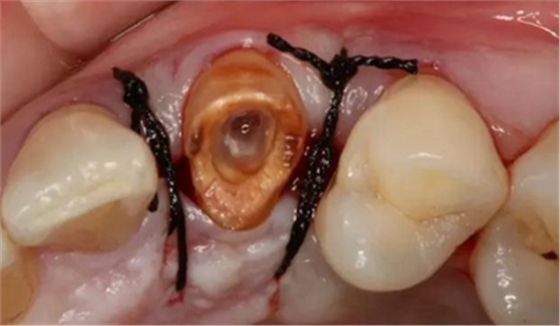

患者女性,55歲,3年前B3纖維樁+鑄瓷全冠修復(fù),一周前牙冠折斷,就診后,發(fā)現(xiàn)纖維樁根管口處折斷,周圍牙齦增生,建議患者行冠延長手術(shù)。首先去除斷端的纖維樁。拍片示牙根長度充足。于是開始冠延長手術(shù)。

因?yàn)槭乔把溃试摶颊邔硇迯?fù)體邊緣必須為齦下,所以3個月后再行修復(fù)。以下為手術(shù)前照片。

以下為術(shù)中照片。

內(nèi)斜切口,頸圈組織,改良垂直褥式縫合。